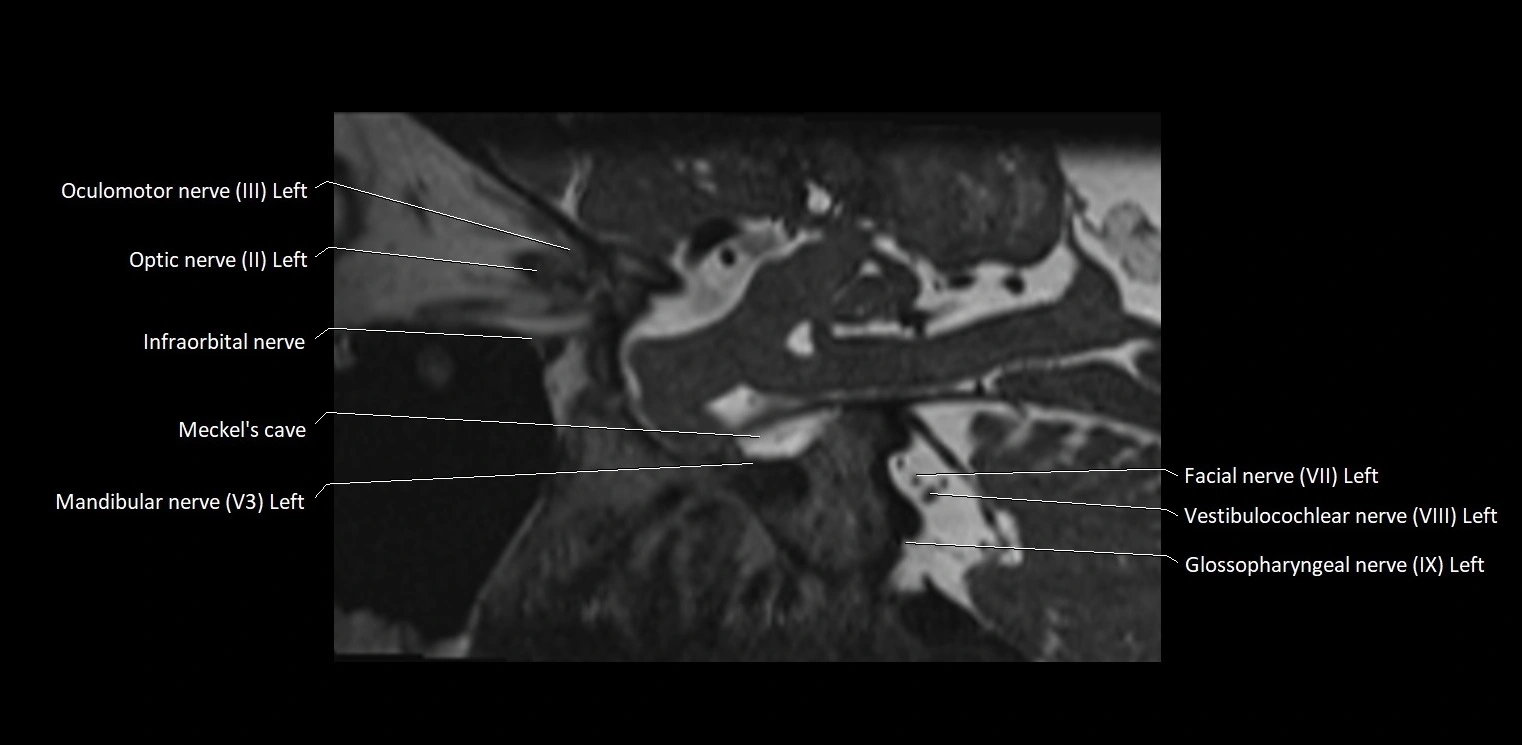

MRI images

image